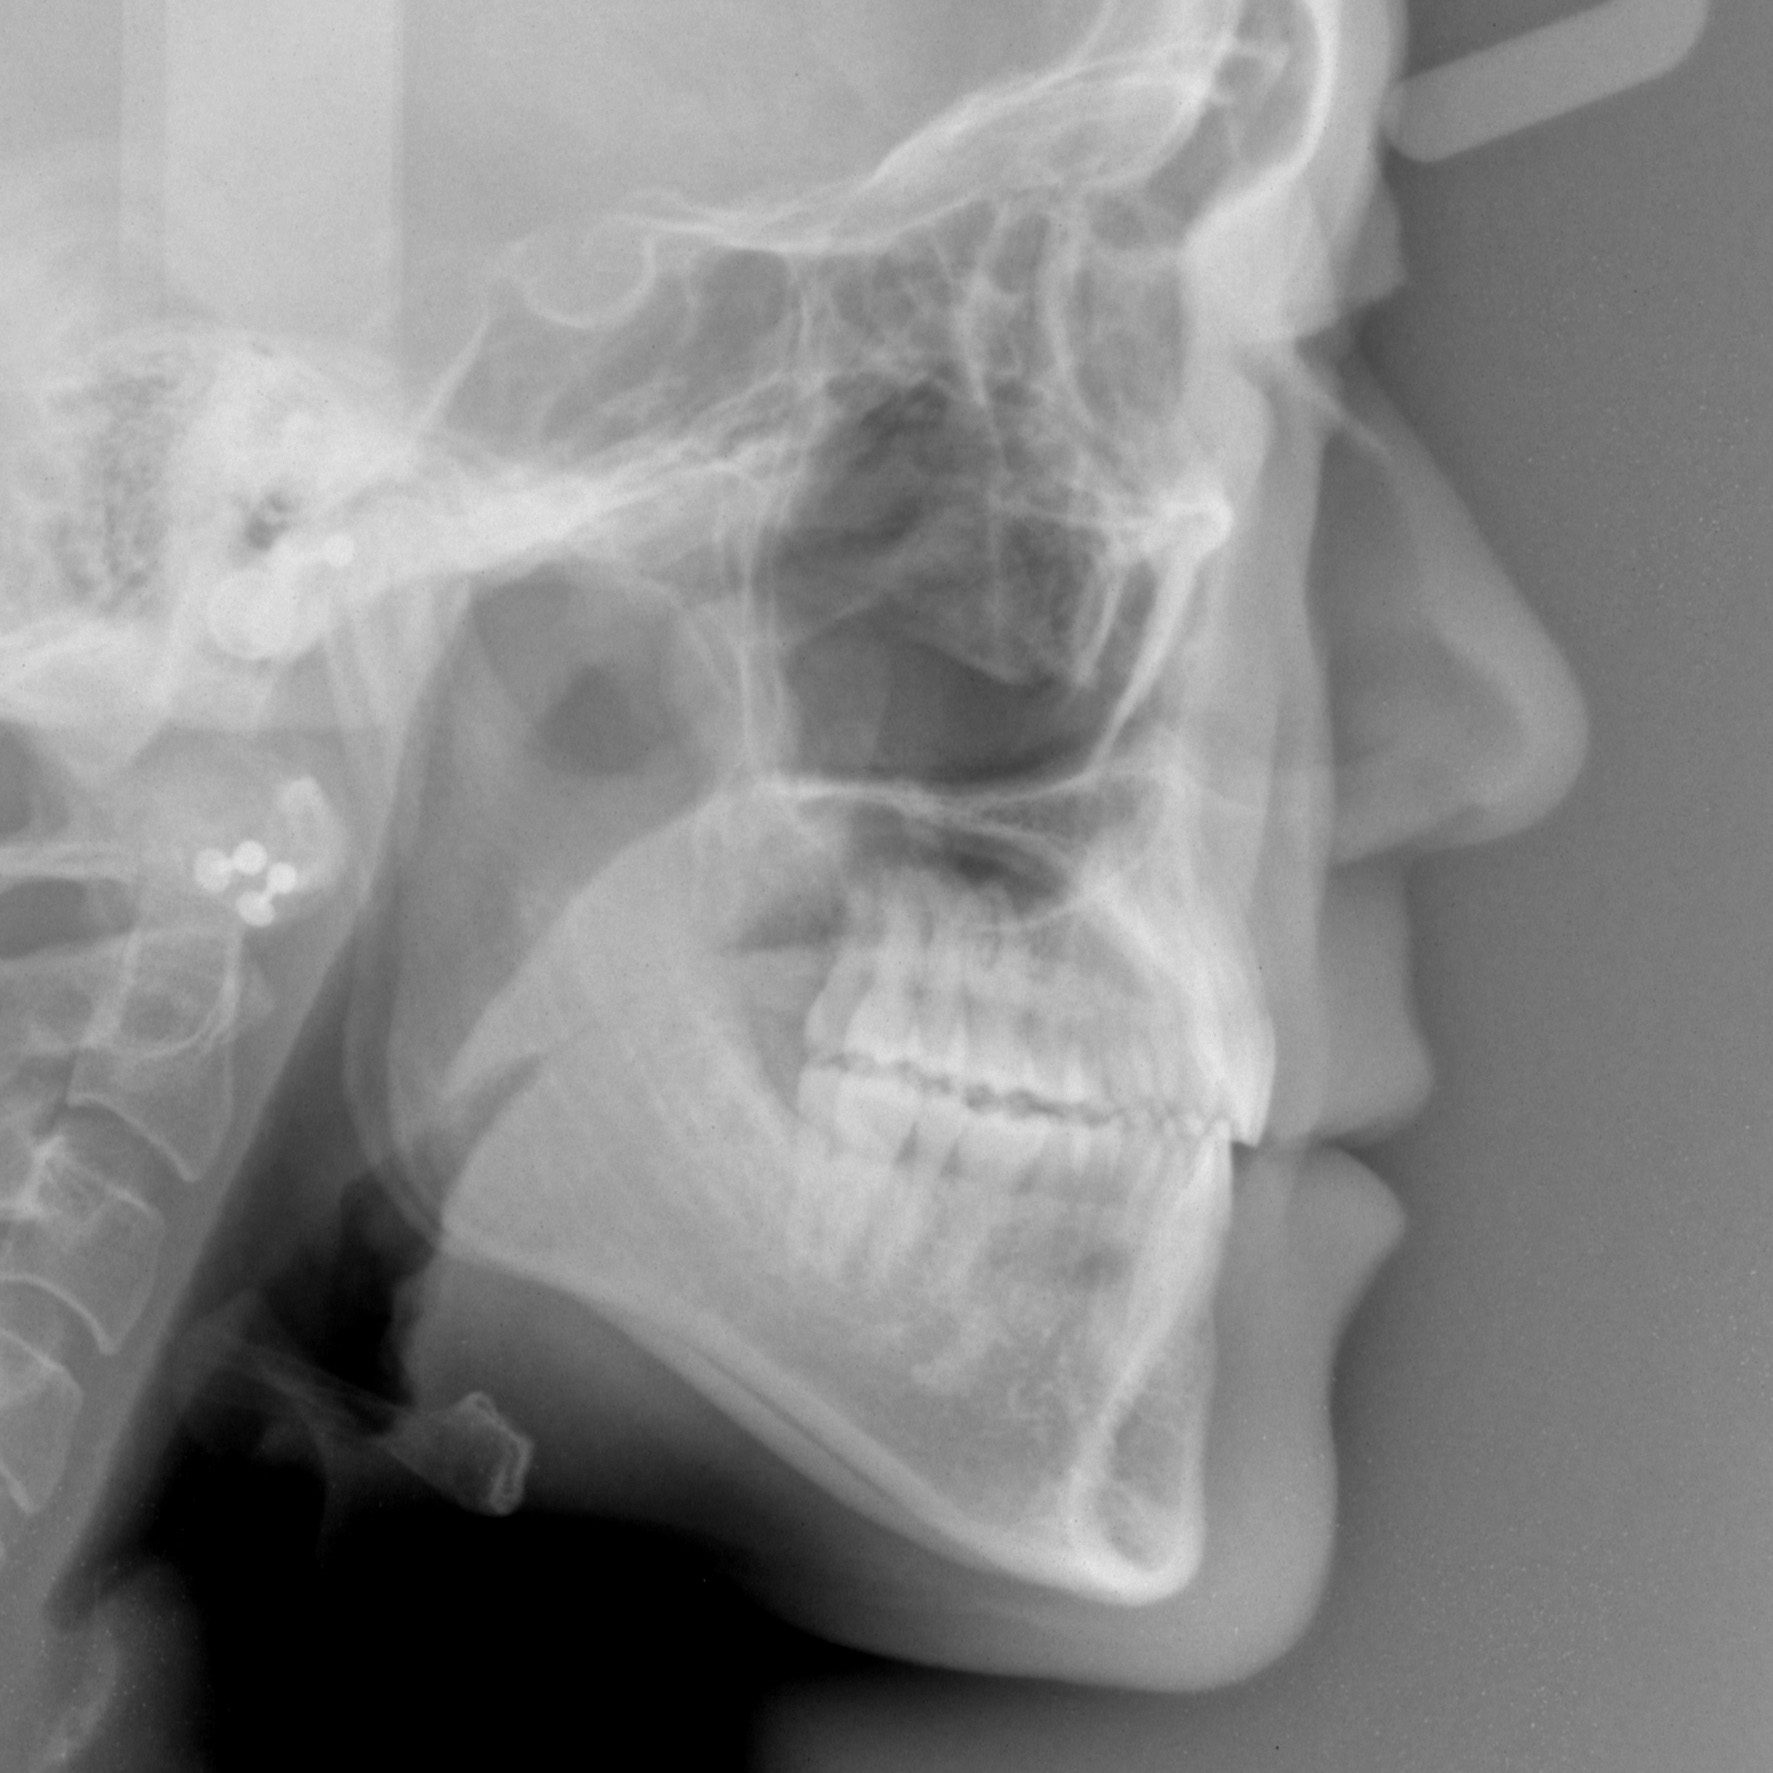

新着情報 1414 治療後セファロ側面 Tweet 投稿日 : 2024年08月06日(火)カテゴリー : コメントを残す コメントをキャンセルメールアドレスが公開されることはありません。 * が付いている欄は必須項目ですコメント 名前 * メール * サイト 36歳 男性「 口もと を 下げてほしい」治療期間24か月(上下顎前突症) ≫